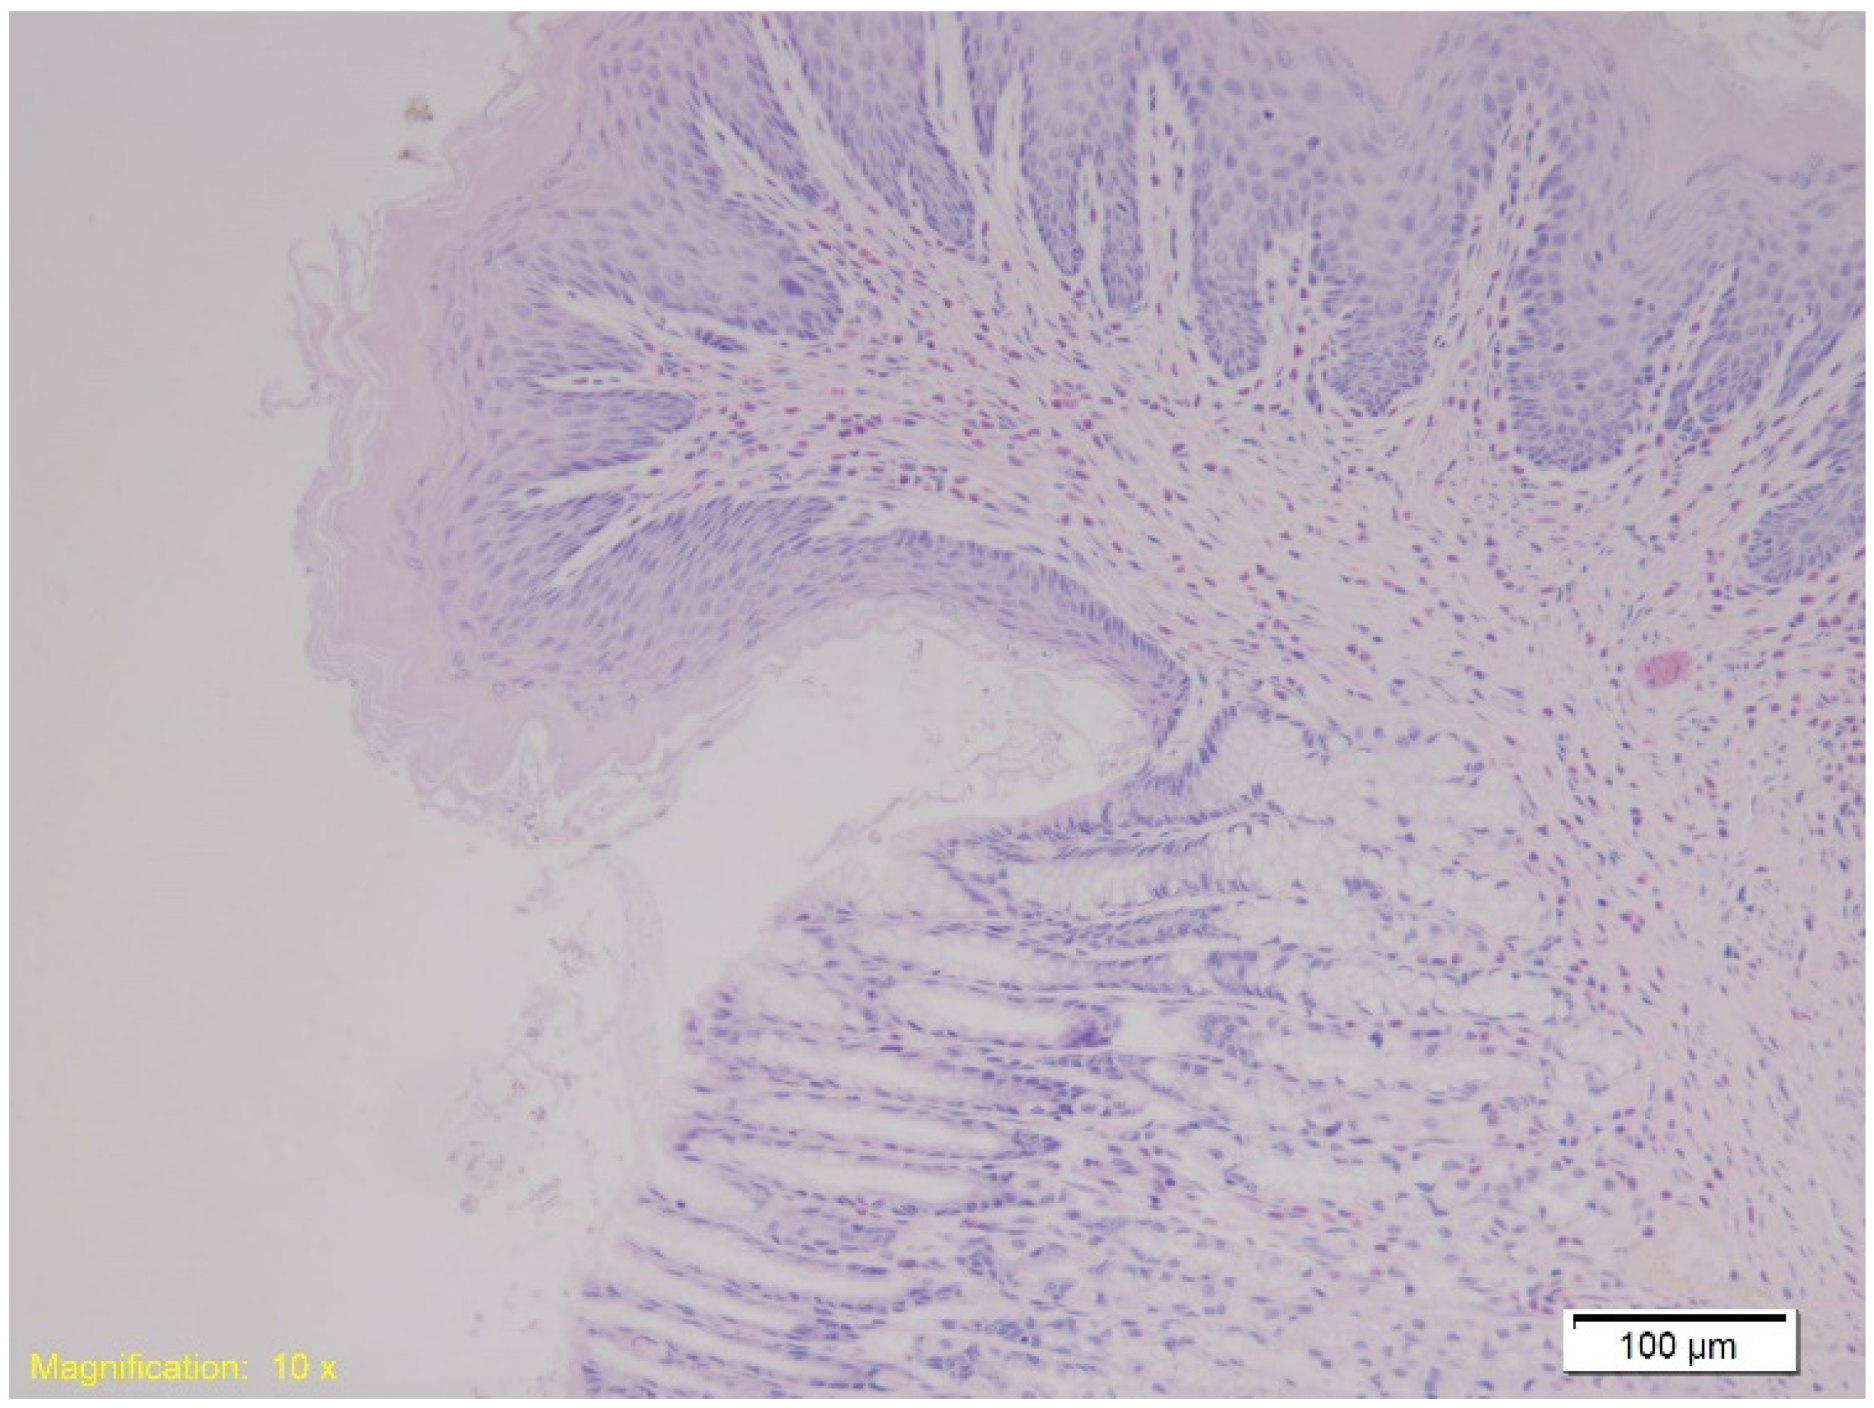

| Organ | Group K (Control) | Group A (Alcohol) | Group B (Benzodiazepine) |

|---|---|---|---|

| Kidney | Hydropic and vacuolar degeneration, congestion; occasional acute tubular injury (eosinophilia, swelling, pyknotic nuclei); minimal lymphocytic infiltrate in interstitium. | Similar findings as Group K; occasional acute tubular injury and lymphocytic infiltrate. | Similar findings as Group K; occasional acute tubular injury and lymphocytic infiltrate. |

| Lungs | Congestion, emphysema, focal atelectasis, and intraalveolar and intraseptal hemorrhage, with emphysema most pronounced. | Slightly increased congestion, intraalveolar and intraseptal hemorrhage; emphysema less pronounced. | Similar to Group A with pronounced congestion, intraalveolar and intraseptal hemorrhage; less emphysema. |

| Heart | Congestion and erythrocyte extravasation in interstitium. | Similar to Group K, with some cardiomyocytes showing finely granular cytoplasm and vacuolar degeneration, suggesting protein denaturation. | Similar to Group K with occasional vacuolar degeneration and protein denaturation in cardiomyocytes. |

| Spleen | Preserved architecture with strong erythrocyte infiltration in red pulp. | Similar findings as Group K. | Similar findings as Group K. |

| Liver | Strong congestion with free erythrocytes in sinusoidal spaces; occasional hepatocyte necrosis with cytoplasmic granulation (potential protein denaturation). | Strong congestion, free erythrocytes in sinusoids; focal hepatocyte necrosis, subcapsular hemorrhage zones. | Strong congestion with similar necrosis and cytoplasmic granulation (suggesting protein denaturation). |

| Gastro-esophagus | Muscle layer hypertrophy, congestion, marked subepithelial eosinophilia. | Similar findings as Group K. | Similar findings as Group K. |